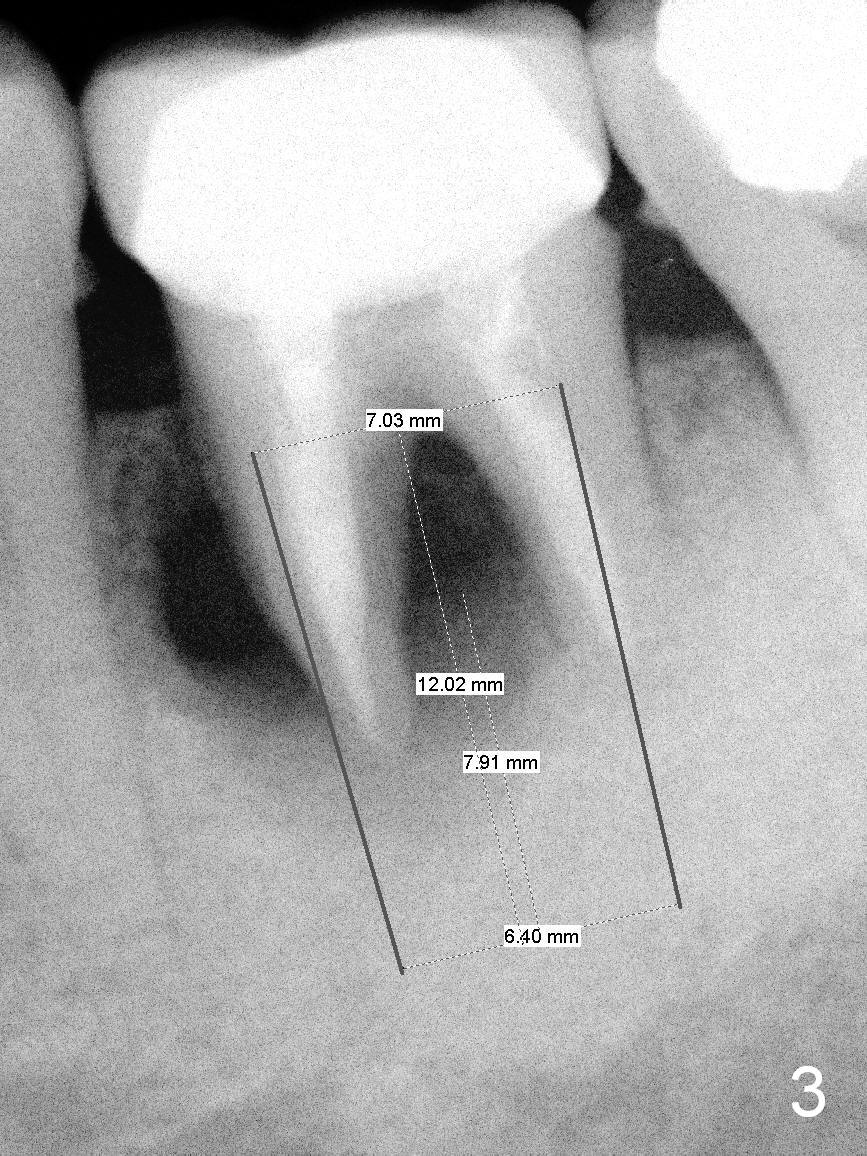

The tooth #19 of a 54-year-old man (FJ) looked normal 2.5 years ago (Fig.1). The patient returns because of 3 fistulae developing around the mesial root of the tooth. Recent PA shows a large radiaolucent defect (Fig.2,3). To place an implant in the middle of the edentulous space, initial osteotomy should be distal because of the large mesial defect.